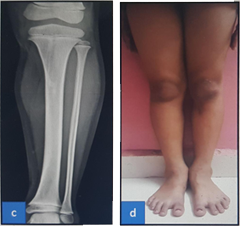

Case - 2

Before

Pre Operative clinical image showing significant swelling and redness & MRI showing intraosseous, subperiosteal and subcutaneous collection.

After

6 month follow up clinical image and X rays showing no leg length descripancy and healed wound.